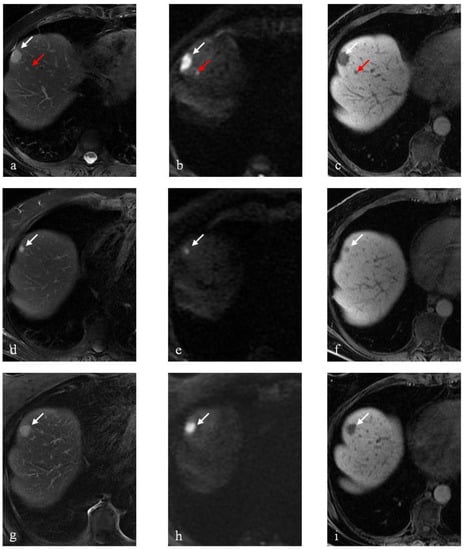

3.1. DLM Results

3.2. RTLM Results

3.3. SRLM Results